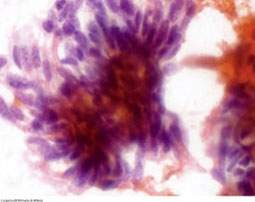

Salivary duct carcinoma, AR and HER2 positive

Salivary Duct Carcinoma

MC in older men; uncommon overall; clinically aggressive

- rsemble comedo ductal carcinoma of the breast

Cyto: Sheets and clusters of large polygonal epithelial cells c obvious malignant features such as large polygonal epithelial cells, irreg nuclear contours c prominent nucleoli

- necrotic background

IHC: AR and HER2 positive

Salivary duct carcinoma, AR and HER2 +